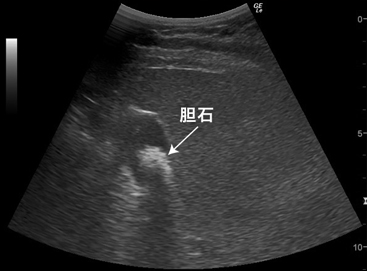

Gallstone

能观察到胆囊内约直径20mm的白色胆结石影像

A white gallstone image of approximately 20mm in diameter is seen in gallbladder